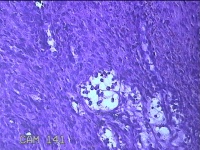

右下唇肿物

性别

女

年龄

12岁

临床诊断

唇囊肿

一般病史

右下唇部肿物一月余。

标本名称

大体所见

灰白粉红色肿物0.8x0.7x0.2cm一个,表面光滑。

图1